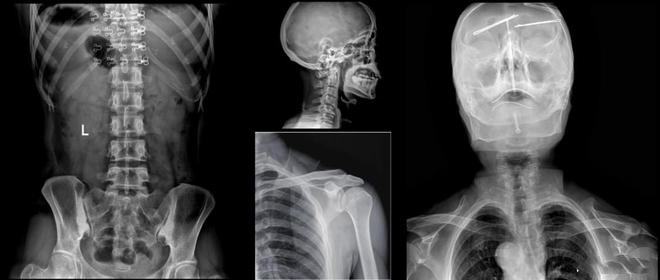

进入21世纪,数字化放射科建设已逐渐成为放射界、医院发展的重点之一。放射科作为日常纷繁医学影像诊断业务的承接科室,最需要的就是在短时间内可以完成高品质成像的高效数字化X线成像系统。浙江大学医学院附属邵逸夫医院放射科引进美诺瓦Staray双立柱智能DR,可用于颈椎、胸部、腹部等站立和头颅、四肢、脊柱等卧位的数字化X摄影,自2020年4月启动至今设备已超24个月,整机保持高开机率稳定运行,有效地提高了放射科的诊断水平和速度,缓解患者的就医压力,提升就诊体验。

美诺瓦Staray双立柱智能DR采用自研核心数字医学影像链技术,成像速度快,放射技师即刻在屏幕上观察到高清图像,病灶一览无余,辅助医生进行更加精准的诊断,AEC自动曝光控制,让拍摄剂量控制更加轻松,省时省力。